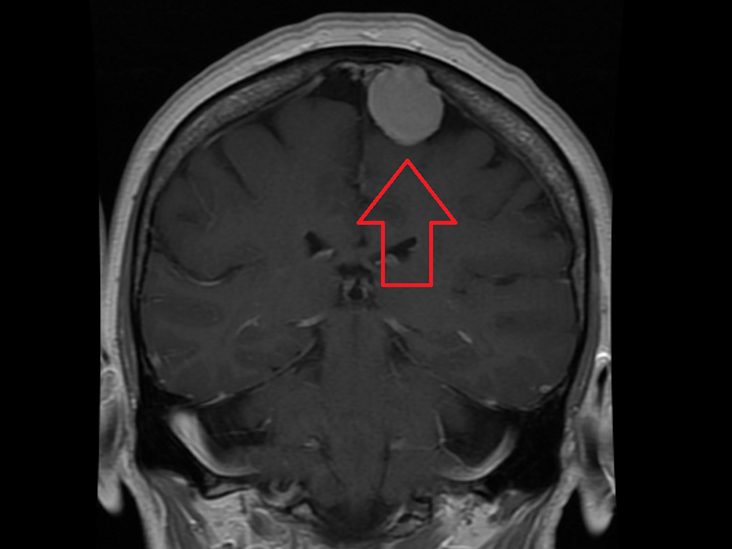

MRI檢查所獲得的圖像清晰、精細、分辨率高,對比度好,信息量大,能更客觀更具體地顯示人體內的解剖組織及相鄰關系,對病灶能更好地進行定位定性,并以其多參數、多序列、多方位和組織分辨率高等特點及能行MR水成像、MRI功能成像和MRI波譜檢查等獨特優(yōu)勢廣泛用于中樞神經系統(tǒng)、頭頸部和軟組織病變的診斷,尤其對早期腫瘤的診斷有很大的價值。

與常規(guī) X 射線和 CT 相比,MRI 可以更清楚地看到大腦、脊髓和神經,以及肌肉、韌帶和肌腱;出于此因,MRI 常用于對膝蓋和肩部損傷進行成像。

在大腦中,MRI 可以區(qū)分白質和灰質,也可用于診斷動脈瘤和腫瘤。由于 MRI 不使用 X 射線或其他輻射,因此當診斷或治療需要頻繁成像時,尤其是在大腦中,它是優(yōu)選的成像方式。然而,MRI 比 X 射線成像或 CT 掃描更昂貴。